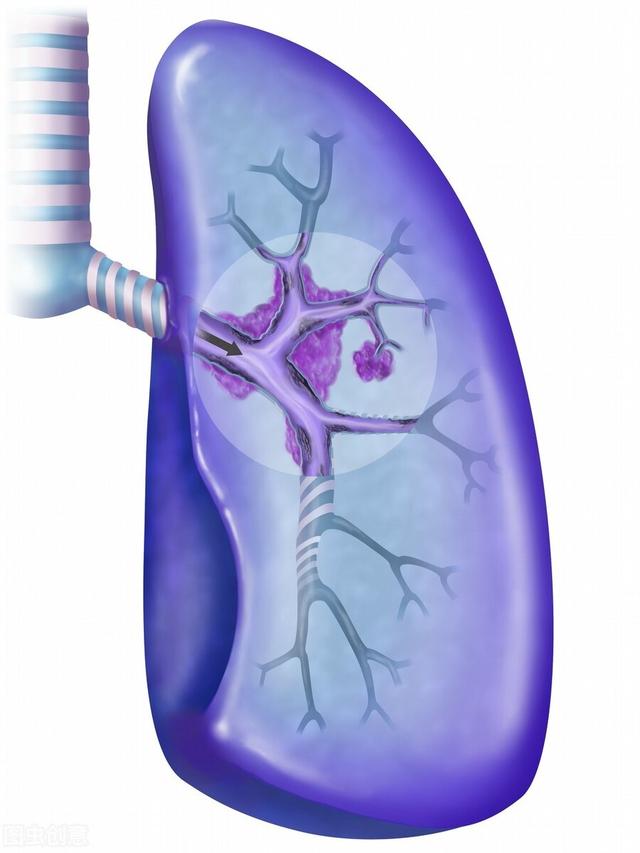

1) L'insuffisance respiratoire, communément appelée manque d'air du patient, est la plus fréquente chez les patients atteints d'un cancer du poumon avancé. Le cancer central du poumon obstrue la trachée et les bronches principales, ce qui rend difficile l'entrée de l'air, et en cas d'atélectasie pulmonaire importante, le patient souffrira progressivement d'essoufflement et de dyspnée. Certains patients développent un épanchement pleural important dû à des métastases pleurales, qui comprime les tissus pulmonaires et empêche la réouverture des poumons. Chez d'autres patients, les lésions pulmonaires sont trop nombreuses et la surface effective de la membrane respiratoire est considérablement réduite. Toutes ces raisons finissent par entraîner une oppression thoracique, un essoufflement, une respiration assise et, finalement, une insuffisance respiratoire.

4) Hémoptysie et asphyxie De nombreux patients atteints de cancer du poumon présentent le symptôme du sang dans les expectorations, en particulier dans le cas du cancer central du poumon, lorsque la tumeur envahit les grands vaisseaux sanguins, une hémoptysie peut se produire, et le sang s'écoule dans les voies respiratoires, provoquant une asphyxie et mettant la vie du patient en danger.

L'homme est capable de respirer de l'oxygène pour survivre sur terre en s'appuyant sur la fonction d'échange d'air des poumons. L'insuffisance pulmonaire est souvent causée par un cancer du poumon avancé, tel que des tumeurs énormes, de grandes quantités d'épanchement pleural, des métastases pulmonaires étendues et une obstruction des voies respiratoires.

(1) Décédé d'une insuffisance respiratoire

Nous avons besoin des deux poumons pour respirer, et si les poumons sont pleins de tumeurs, ils perdent leur capacité à respirer, et le cancer peut également bloquer les voies respiratoires, et il y a aussi du liquide pleural, dont une grande quantité comprime les poumons et provoque des difficultés respiratoires. Si les poumons ne peuvent pas fonctionner, il n'y aura bientôt plus assez d'oxygène et les organes du corps entier seront privés de sang et d'oxygène et finiront par mourir.

1) Insuffisance respiratoire :Comme nous le savons tous, le poumon est le principal organe respiratoire et les patients atteints d'un cancer du poumon, en particulier ceux qui sont à un stade avancé, ont des difficultés à respirer car les cellules cancéreuses détruisent les tissus pulmonaires normaux. Si les cellules cancéreuses s'étendent à l'ensemble du corps, comme les métastases cérébrales, les métastases hépatiques ou les métastases osseuses, elles entraînent une perturbation de l'environnement interne de l'ensemble du corps, ce qui provoque également une insuffisance respiratoire. Pour la grande majorité des patients atteints d'un cancer du poumon avancé, une fois que l'insuffisance respiratoire se produit, ils peuvent avoir atteint le stade terminal, et leurs familles doivent être préparées psychologiquement.

3. hémoptysie provoquant une asphyxie ou un choc :La tumeur bloque le passage des gaz, irrite les parois bronchiques et la trachée tente d'expulser le corps étranger, ce qui provoque une toux, parfois accompagnée de sang dans les expectorations, ce qui constitue une hémoptysie. Lorsque la tumeur envahit les gros vaisseaux sanguins, elle peut entraîner une rupture des vaisseaux sanguins et une hémoptysie, l'afflux de sang dans la pièce provoquant l'asphyxie ou l'état de choc du patient, ce qui met sa vie en danger. En règle générale, si le patient présente des symptômes d'hémoptysie, cela signifie que la maladie a atteint un stade avancé.